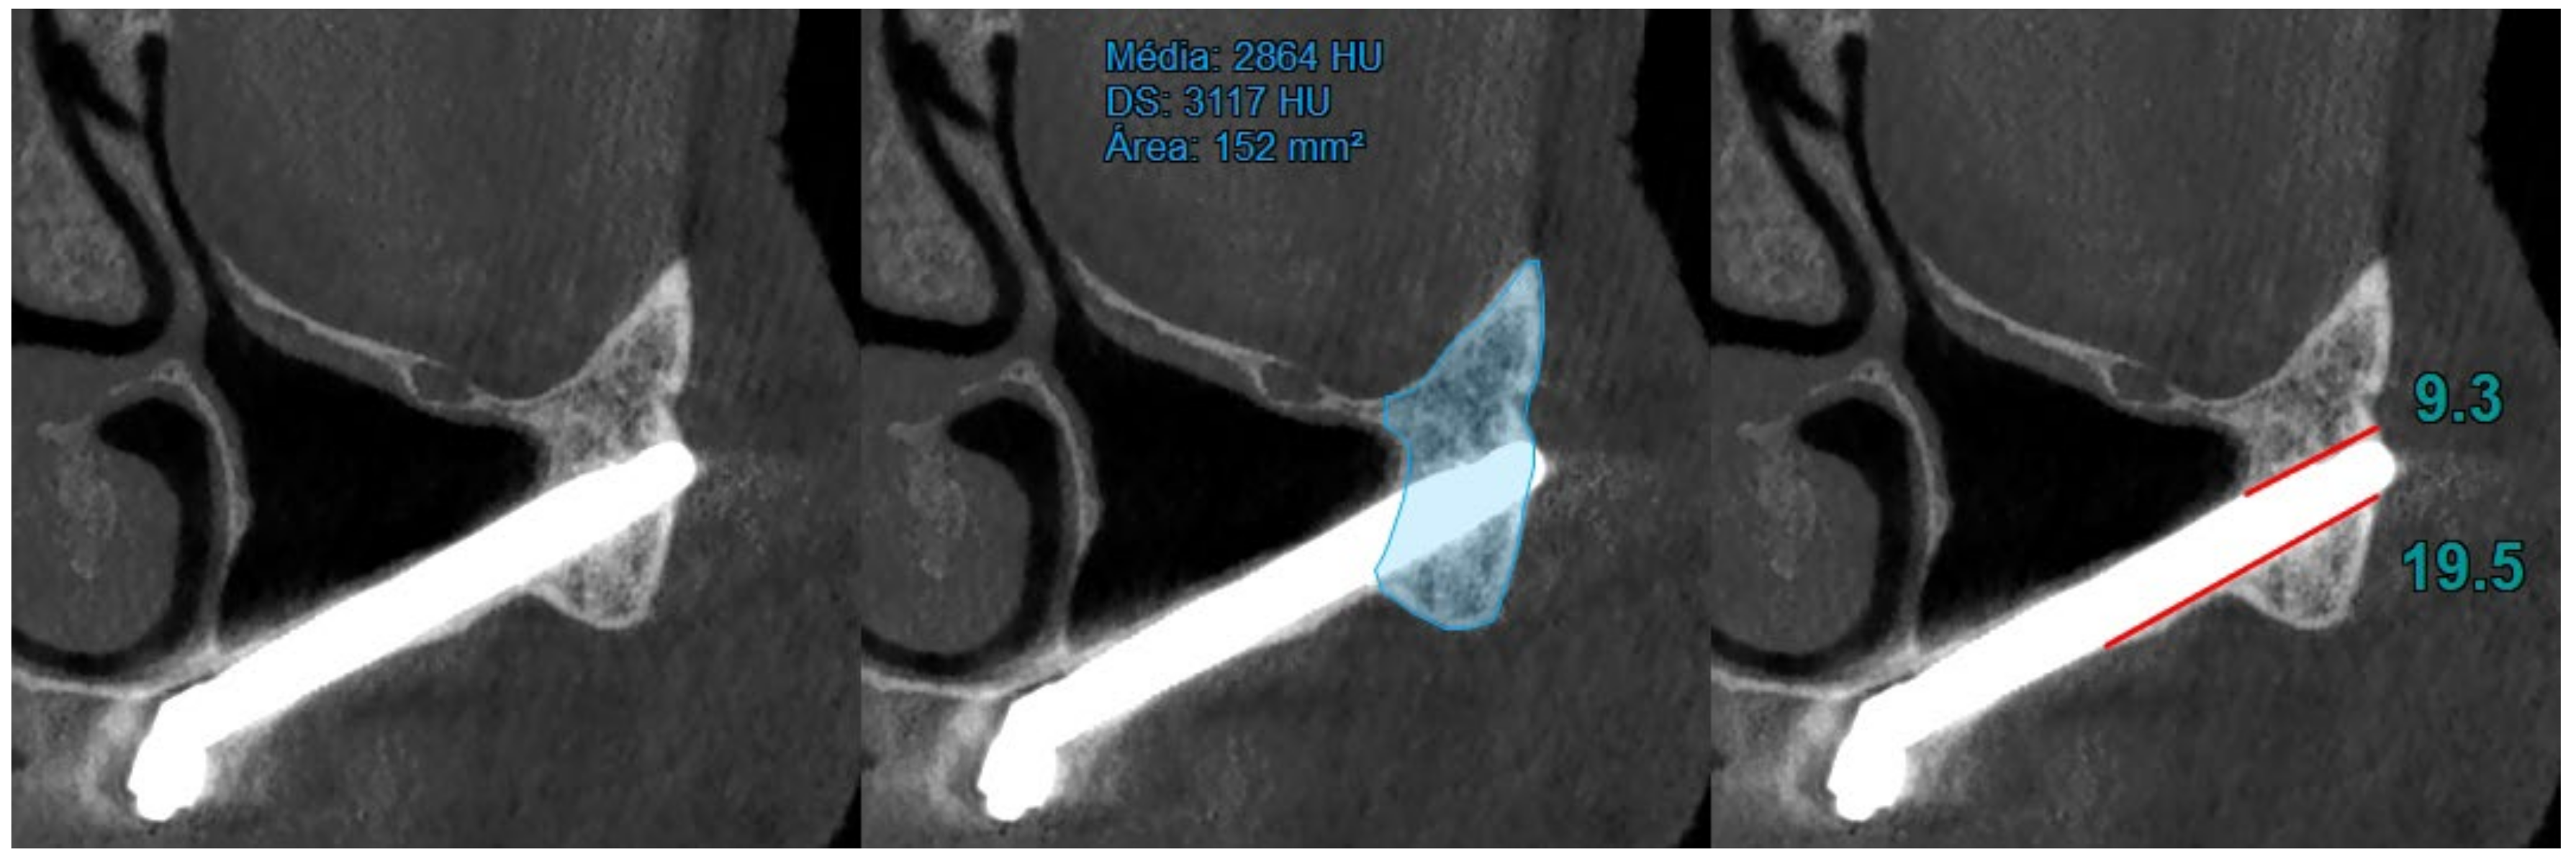

- At T2 (120 months of follow-up), the area and density of the zygomatic bone, the upper contact distance between the zygomatic bone and the zygomatic implant, and the lower contact distance between the zygomatic bone and the zygomatic implant were also evaluated (Figure 3).

| Zygomatic Bone Density (1st Quadrant) (HU) Mean ± SD, Newtons | T0: 1077.23 ± 264.90; T1: 2642.06 ± 550.33; T2: 2853.04 ± 530.26. |

| Zygomatic Bone Density (2nd Quadrant) (HU) Mean ± SD, Newtons | T0: 1030.46 ± 314.13; T1: 2457.86 ± 561.85; T2: 2696.60 ± 583.29. |

| Upper Contact Distance between Zygomatic Bone and Zygomatic Implant (1st Quadrant) (mm) Mean ± SD, Newtons | T0: No valid cases; T1: 9.01 ± 3.19; T2: 9.10 ± 3.23. |

| Upper Contact Distance between Zygomatic Bone and Zygomatic Implant (2nd Quadrant) (mm) Mean ± SD, Newtons | T0: No valid cases; T1: 8.04 ± 3.02; T2: 8.20 ± 3.19. |

| Lower Contact Distance between Zygomatic Bone and Zygomatic Implant (1st Quadrant) (mm) Mean ± SD, Newtons | T0: No valid cases; T1: 13.70 ± 4.74; T2: 13.61 ± 4.62. |

| Lower Contact Distance between Zygomatic Bone and Zygomatic Implant (2nd Quadrant) (mm) Mean ± SD, Newtons | T0: No valid cases; T1: 14.69 ± 4.96; T2: 14.65 ± 4.98. |